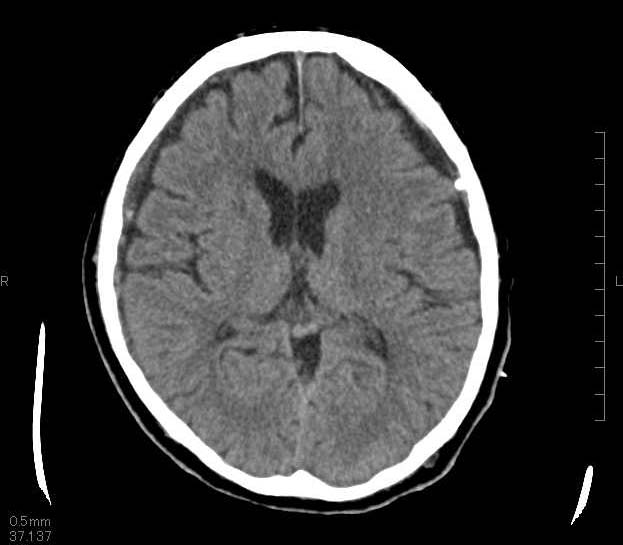

慢性硬膜下血腫(まんせいこうまくかけっしゅ)とは?

頭をぶつけたりした後、数週間してから血が溜まってくる不思議な袋状のかたまりです。

自然に治ることもありますが、大きい場合は手術が必要となります。

穿頭(せんとう)血腫洗浄ドレナージ術

1円玉サイズの穴を頭の骨に開けて、そこから細い管(ドレーン)を入れて中身の血性液を除去洗浄します。内容液を抜くために、ドレーンを残したまま傷を閉じます。ドレーンは翌日に抜去します。